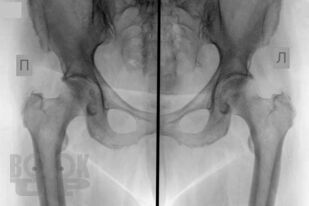

В основу книги положен многолетний опыт ультразвуковых исследований тазобедренного сустава в многопрофильной клинике с развитыми ревматологической и ортопедической службами. Проанализирован опыт отечественных и зарубежных авторов, суммированы результаты многочисленных оригинальных собственных исследований. Подробно освещены вопросы топографической и ультразвуковой анатомии тазобедренного сустава, технические особенности проведения исследования в том числе с использованием контрастных препаратов, проведения внутрисуставных инъекций под контролем ультразвукового исследования. Подробно описаны особенности ультразвуковой визуализации неизмененного тазобедренного сустава, широкого спектра патологических состояний и заболеваний дегенеративно-дистрофического, травматического, воспалительного генеза при использовании новейших и инновационных технологий эхографии. Дано подробное описание ультразвуковой картины при различных состояниях сустава: от асептического некроза головки бедренной кости, артрита, трохантерита, бурситов до бедренно-ацетабулярного импинджмента, ARS- и хамстринг-синдромов. В монографии представлены рациональные варианты и алгоритм диагностического поиска при патологии тазобедренного сустава с применением методов лучевой визуализации, определено оптимальное место ультразвукового исследования, даны подробные варианты описательной и заключительной частей ультразвуковых протоколов.